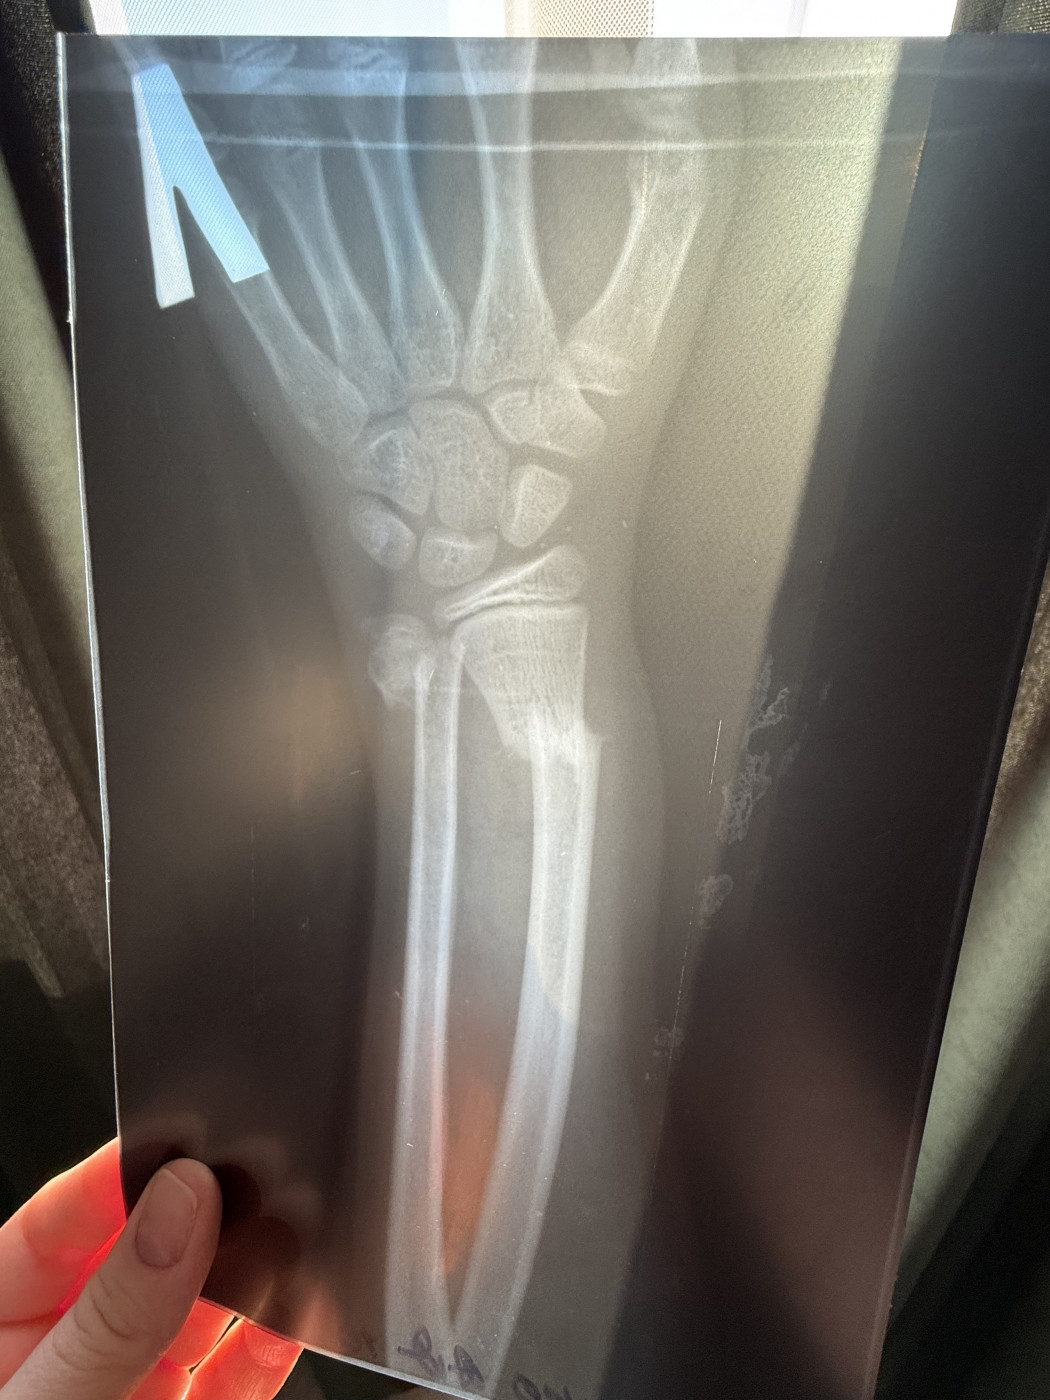

Перелом двух костей предплечья.   1 ответ

Здравствуйте. Прошу консультации у Вас знающие, уважаемые специалисты. Данный прелом относится к нижней трети (лучезапястный сустав, кисть) или к средней трети предплечья?